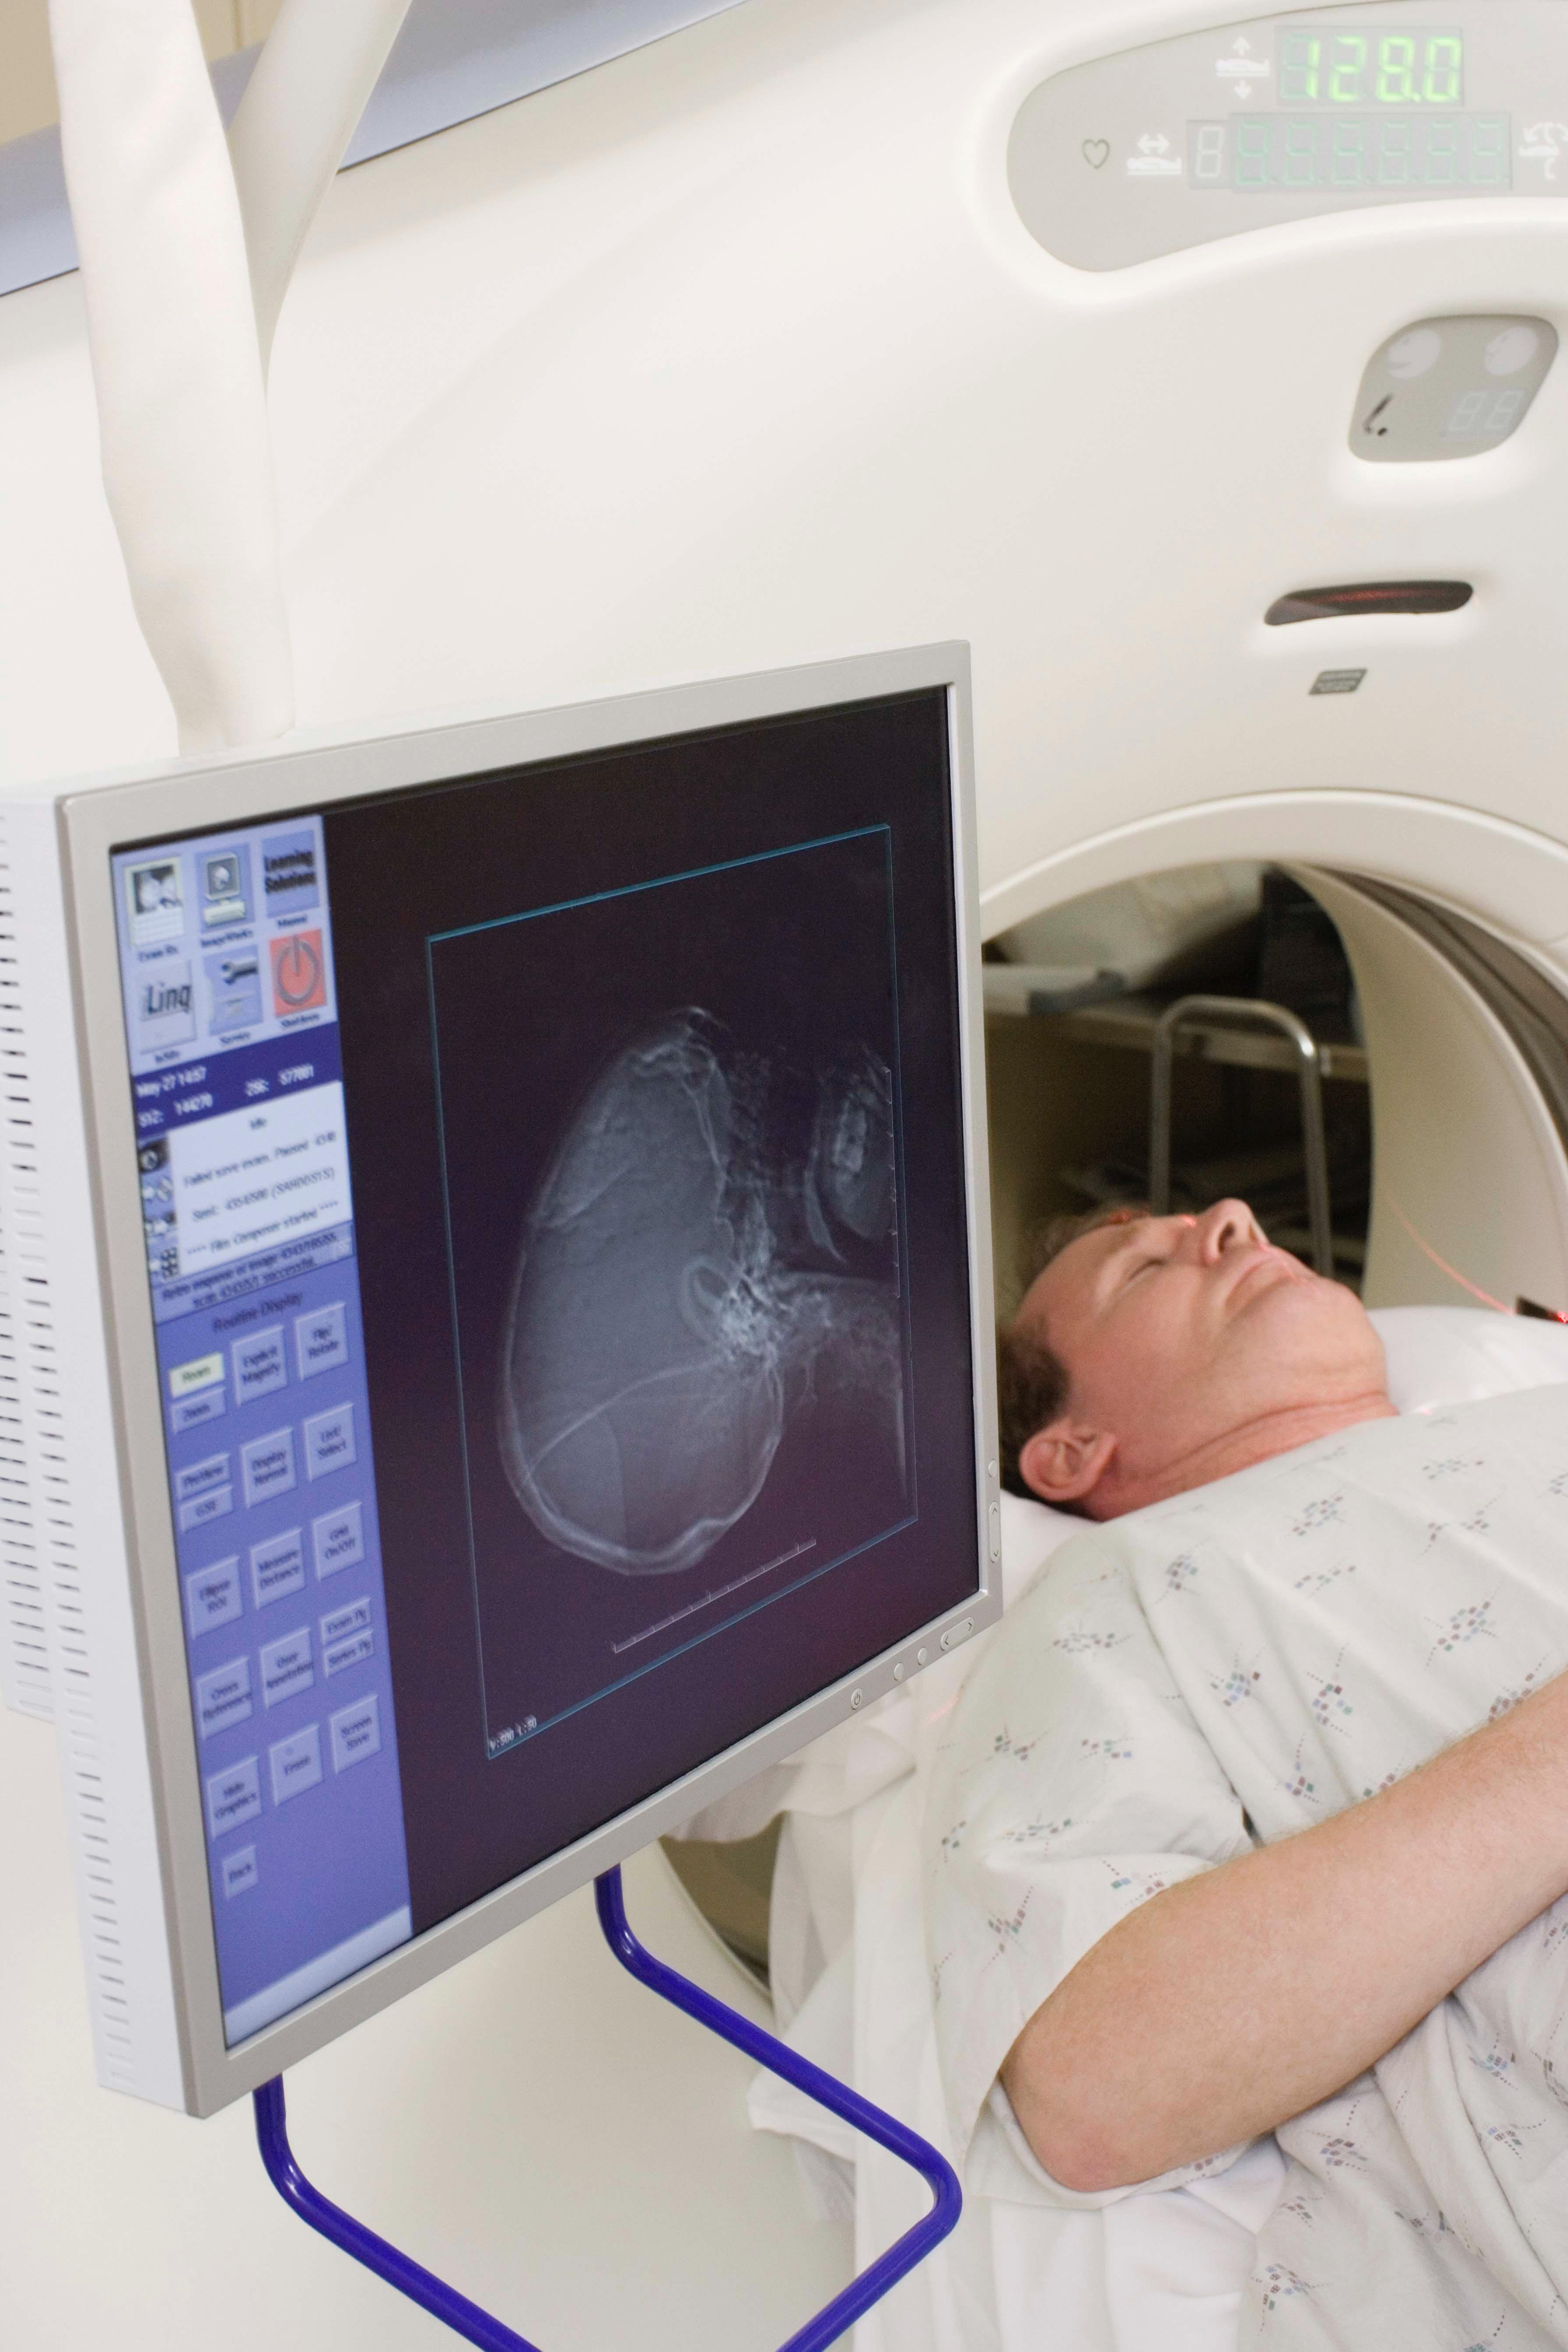

Rezonans magnetyczny głowy to test obrazowania diagnostycznego, który pozwala na uzyskanie bardzo szczegółowych obrazów mózgu. Ta nieinwazyjna procedura pozwala na wykrycie wielu chorób i zaburzeń mózgu, takich jak guzy, urazy, choroby zapalne i wiele innych. W niniejszym artykule omówimy, jak przebiega badanie rezonansem magnetycznym głowy, jakie zmiany może wykryć i jak się do niego przygotować.